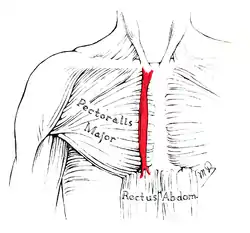

The sternalis muscle as it lies on top the pectoralis major.

The sternalis muscle as it lies on top the pectoralis major. Sternalis muscle visible in an individual who also has an accessory abdominal pectoralis major, and an axillary arch of the latissimus dorsi.